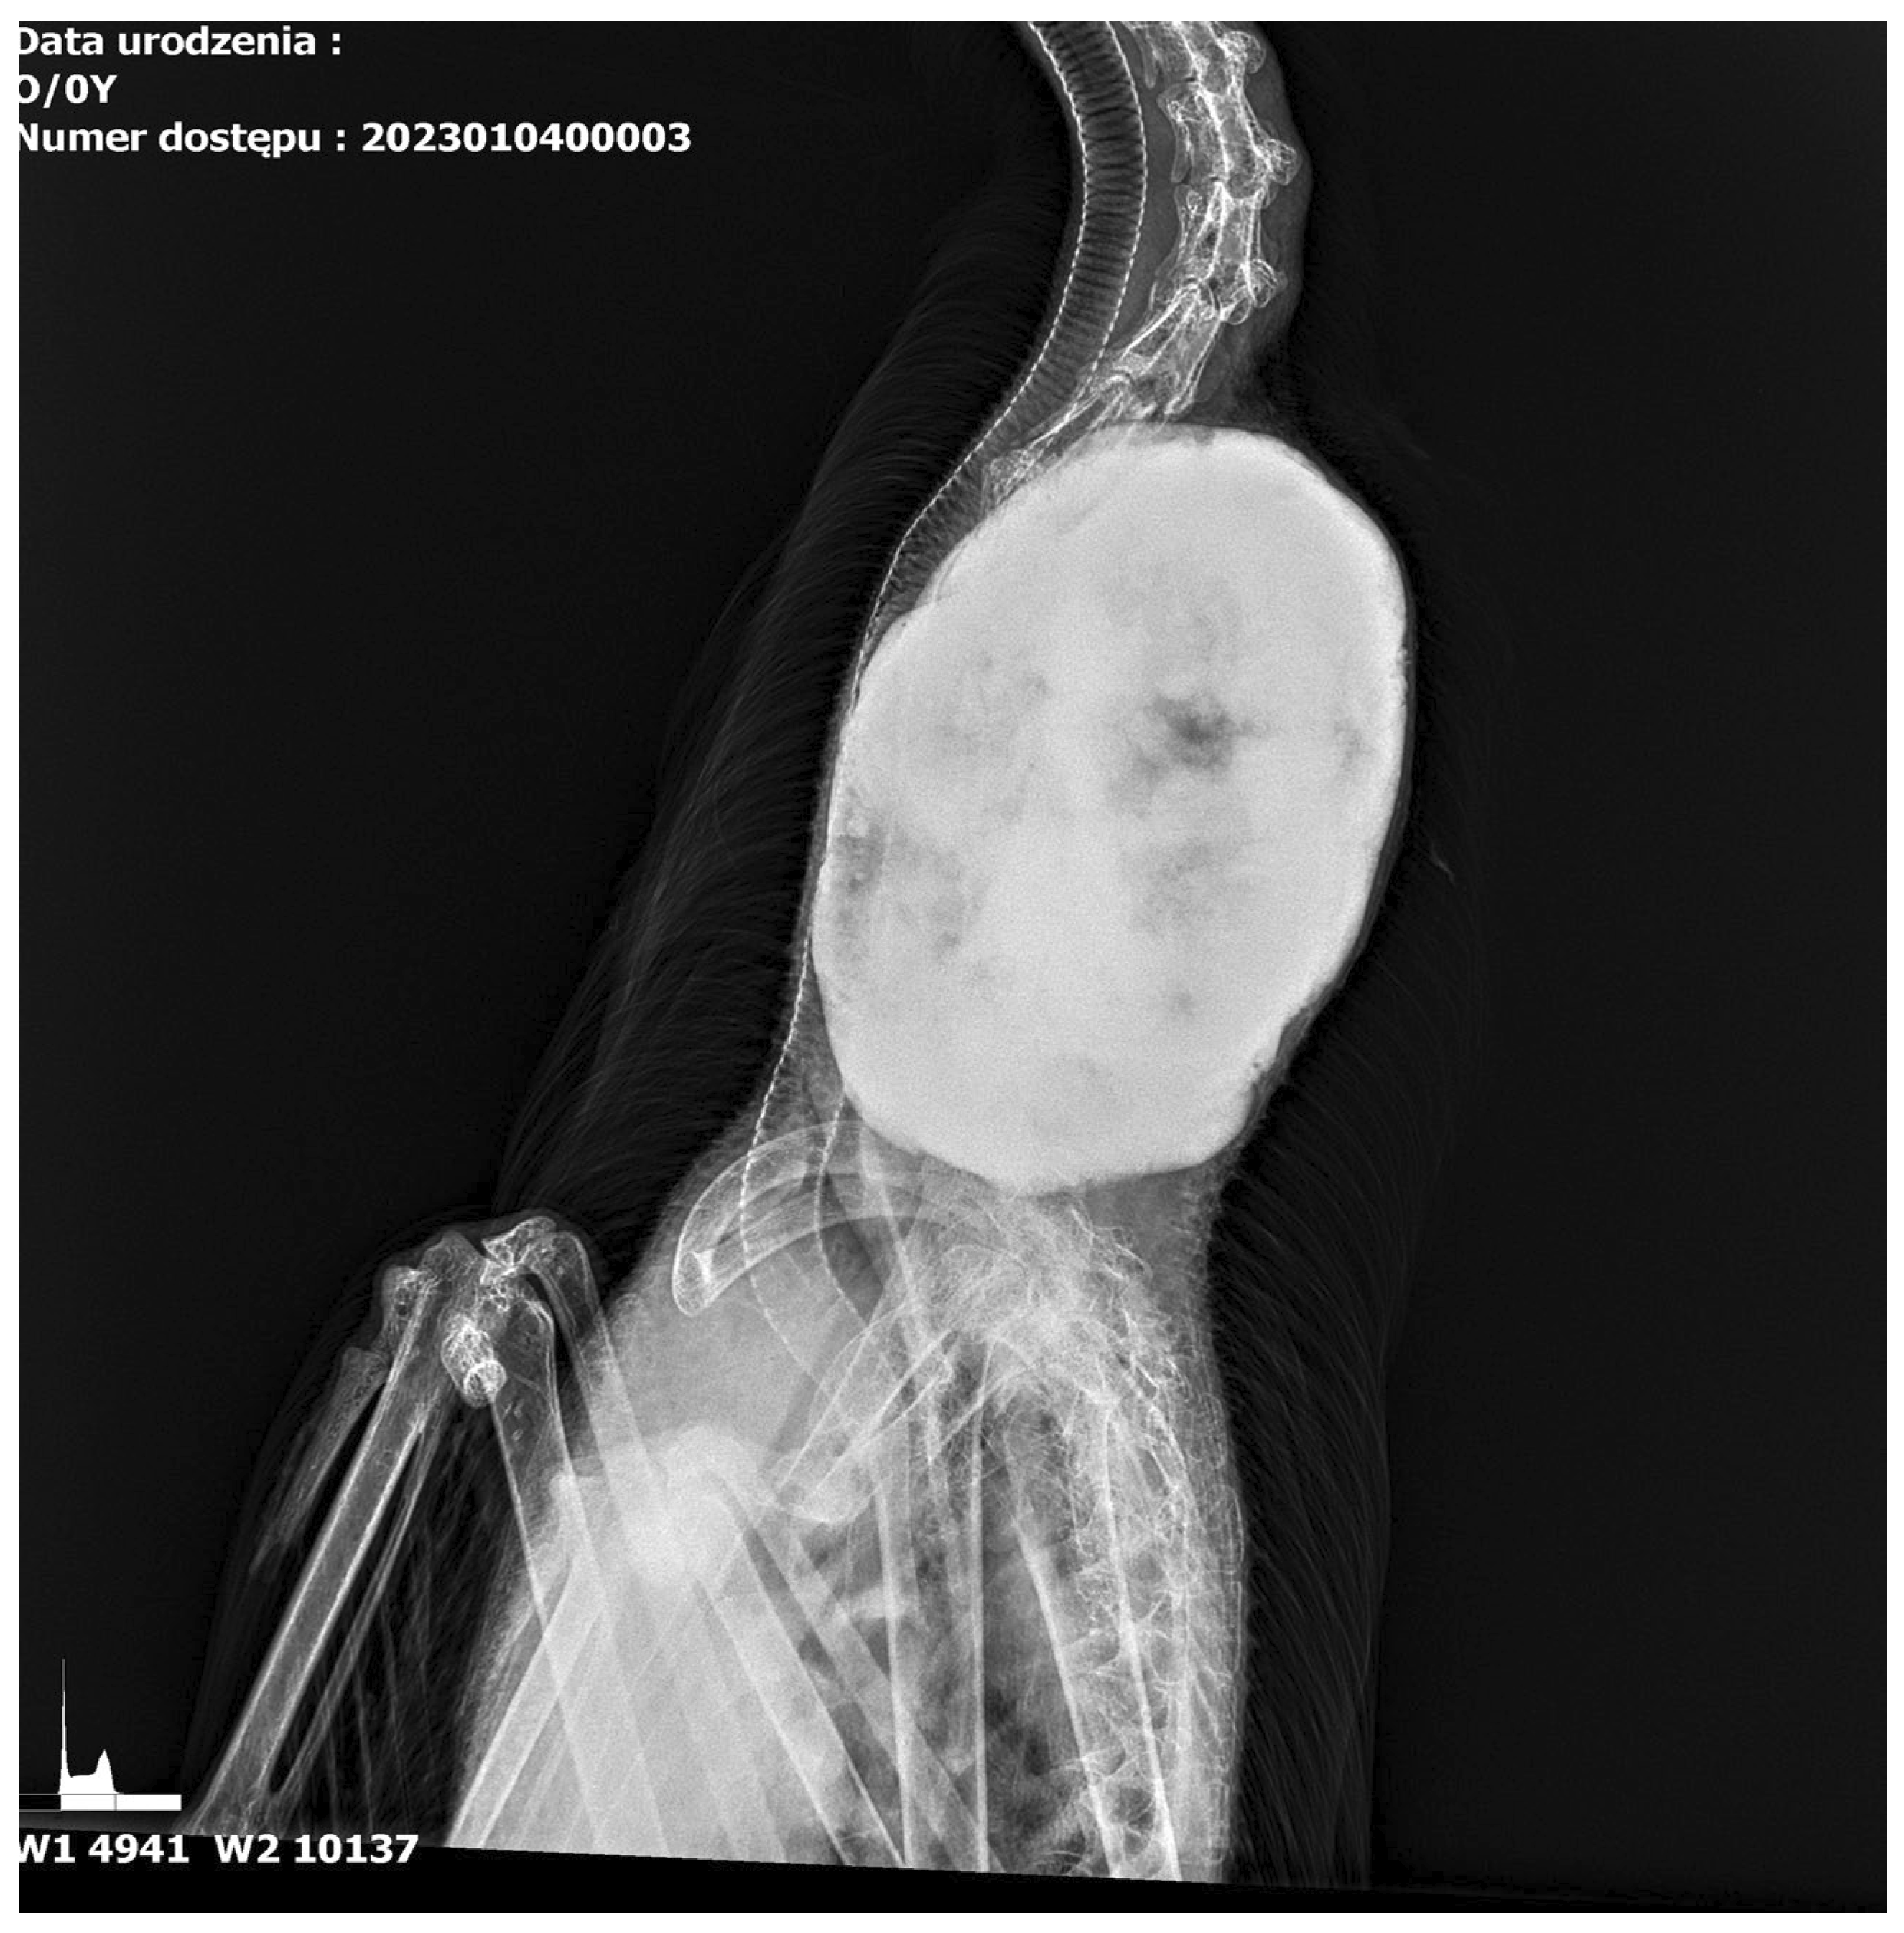

3.1. Results of Radiological Examination